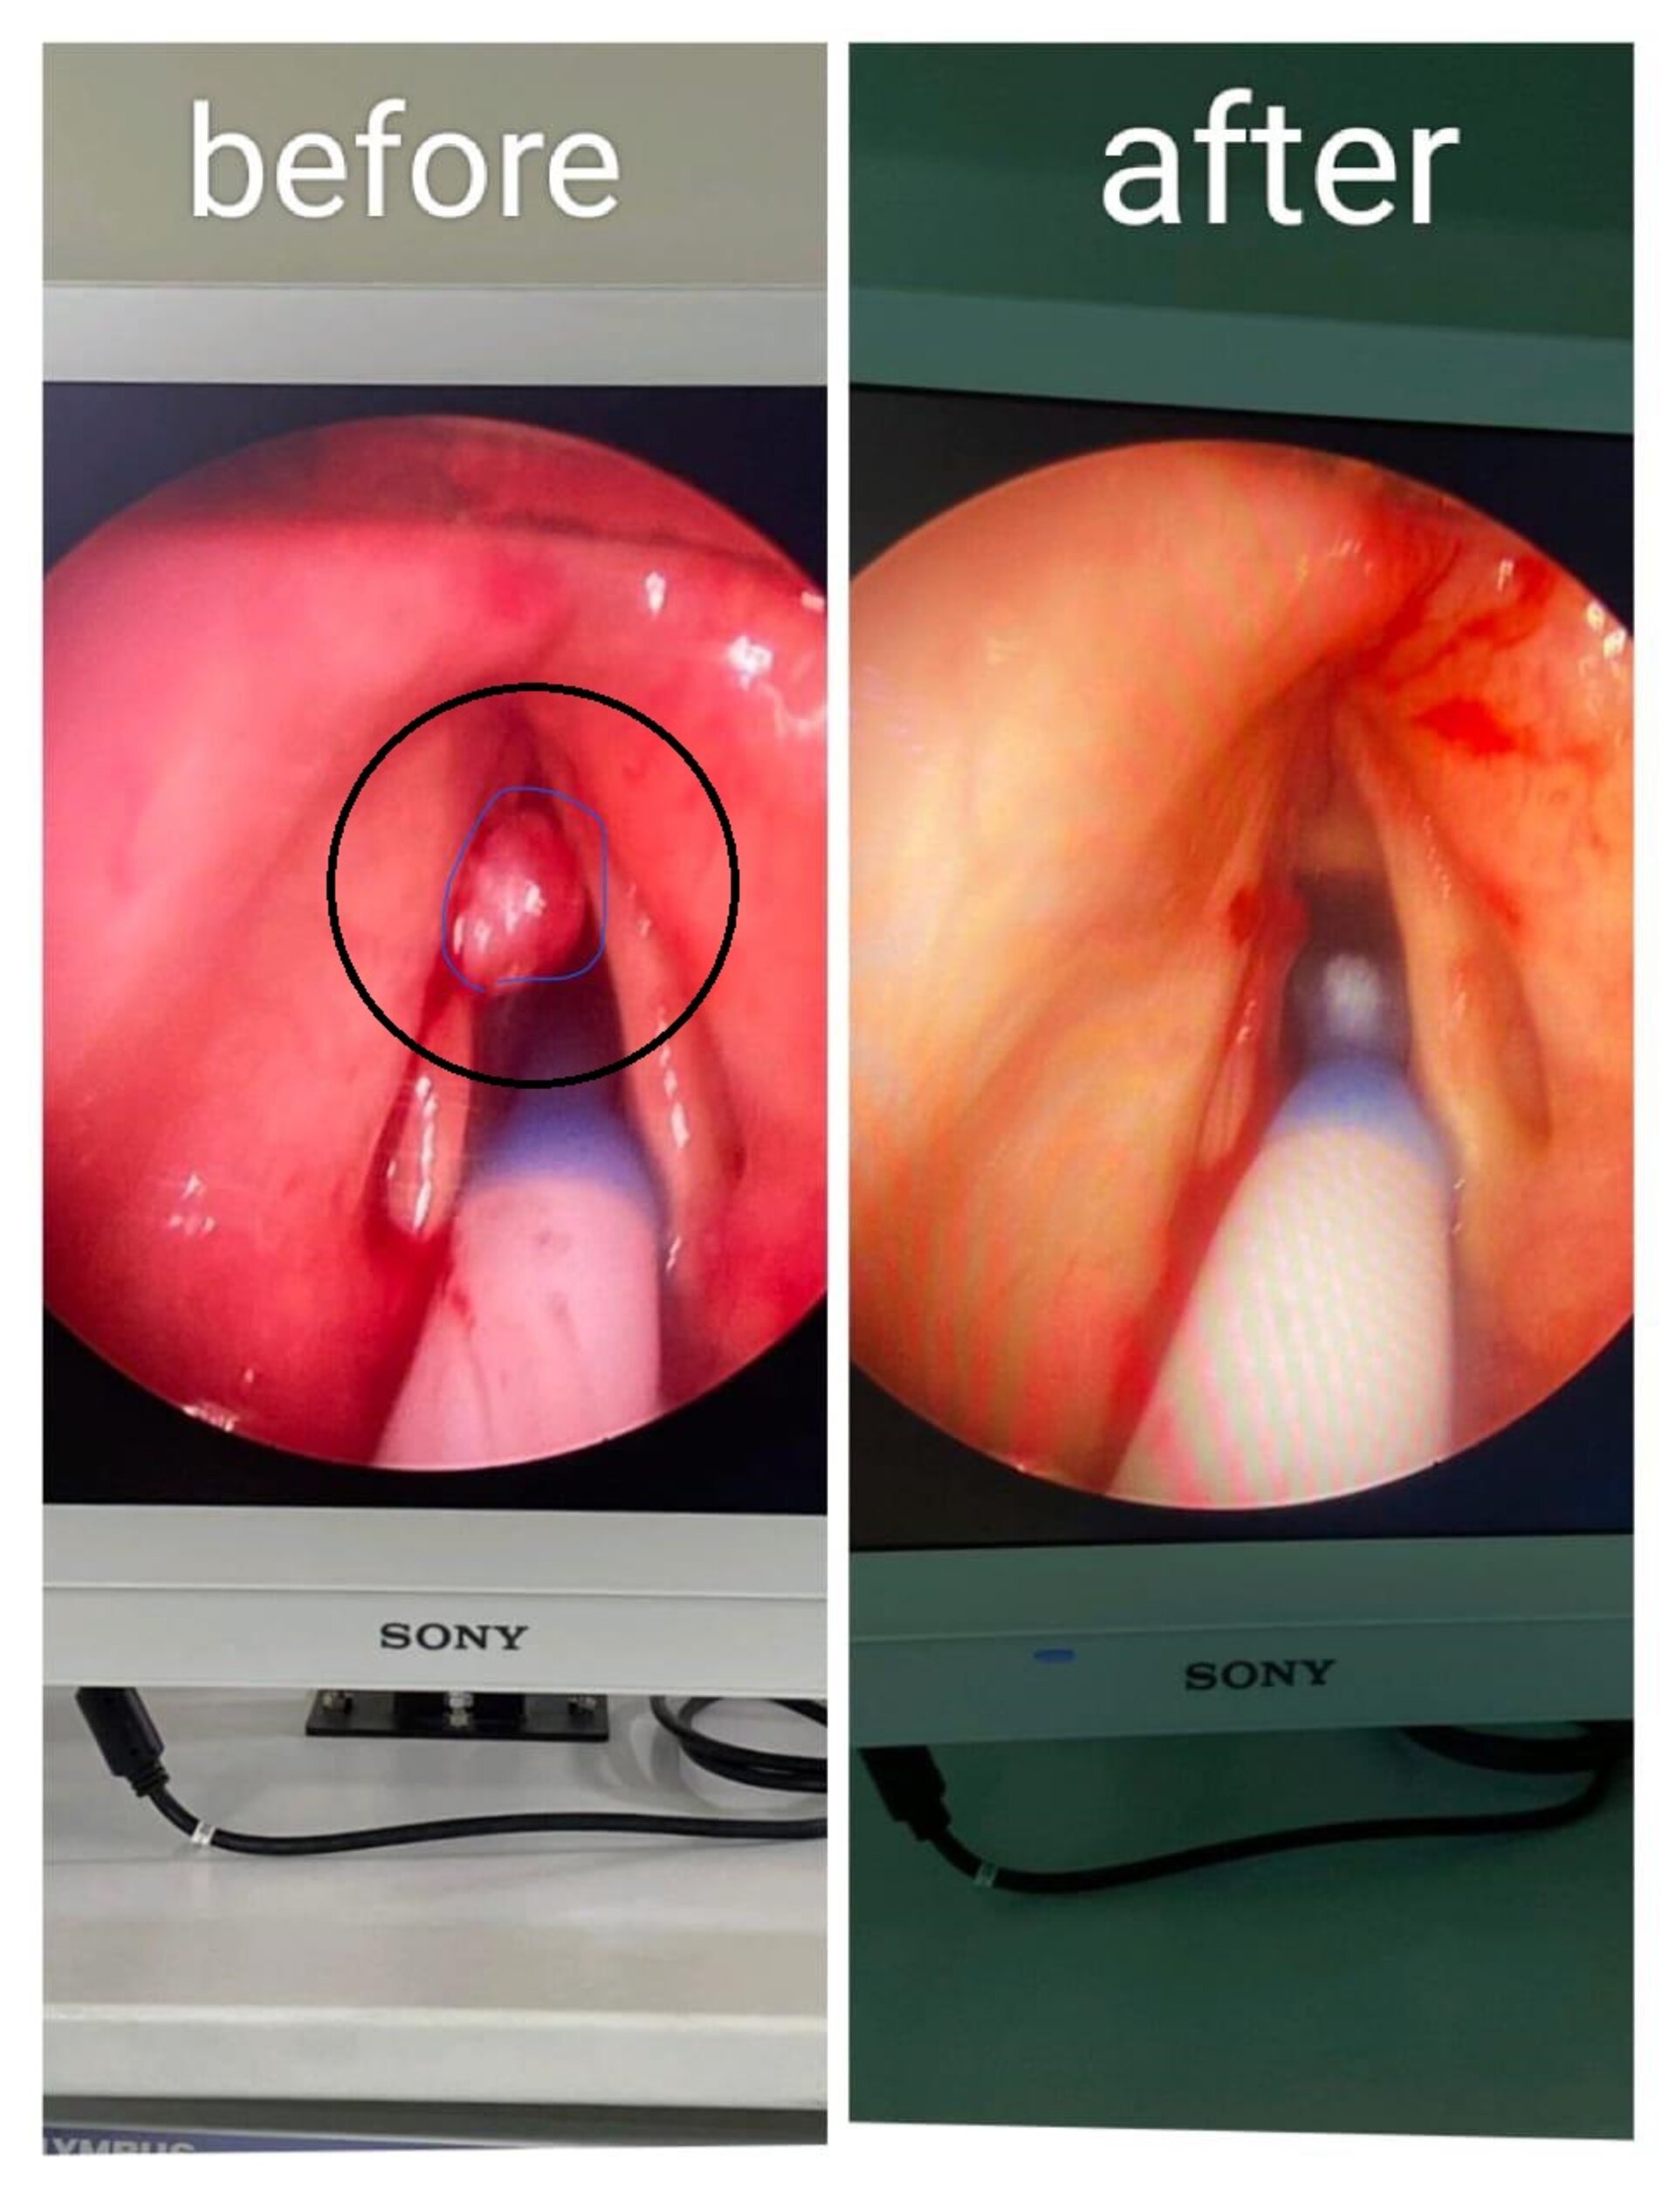

Successful High-Risk Vocal Cord Surgery by Dr. Monika Bhagat in Pune

Dr. Monika Bhagat, a renowned Consultant ENT and Cochlear Implant Surgeon in Pune, successfully performed a micro laryngoscopy-guided excision on a 78...